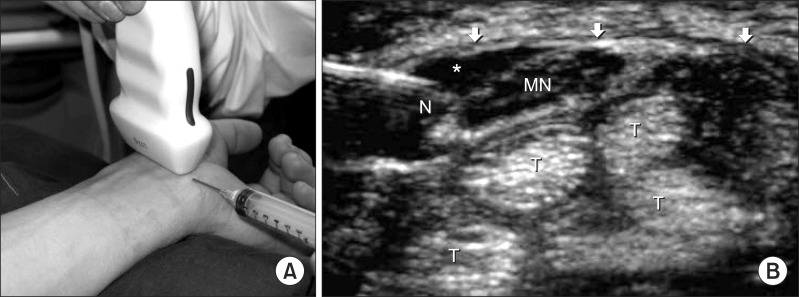

٤- أبره كرتزون حول العصب المتوسط

احد الحلول الفعاله الحقن بالكرتزون حول العصب المتوسط تحت الأشعه فوق الصوتيه